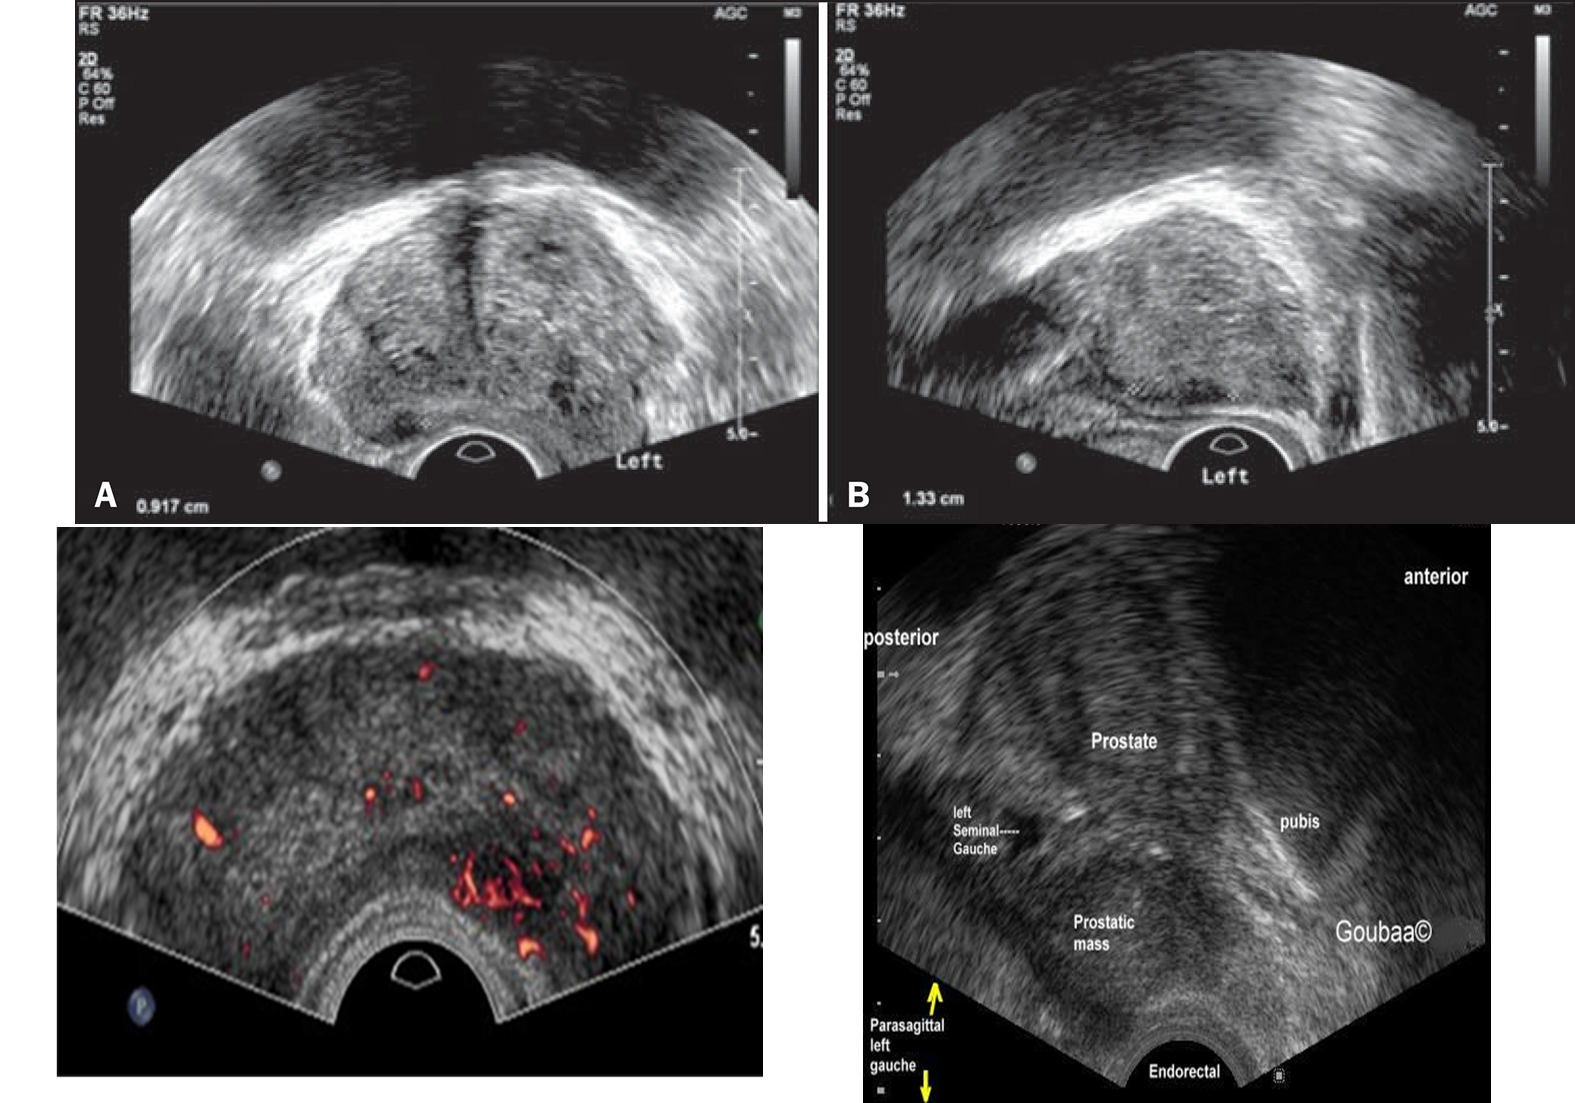

prostatic carcinoma appearance

hypoechoic, peripherally located

can infiltrate and extend beyond capsule

prostate ca

what is better at prostate imaging

MRI

what does MRI do better

detect

prevent 40% unnecessary biopsies